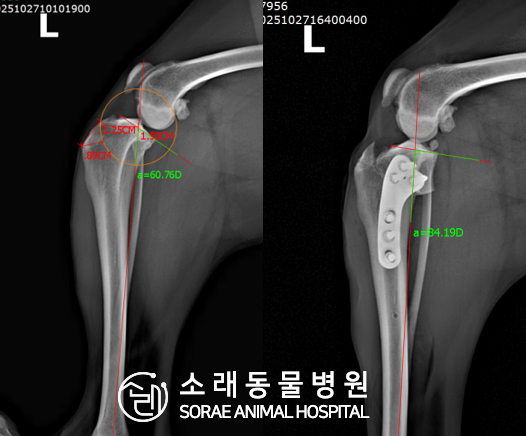

계산식으로 사전에 계획해두었던 플랜에 따라 경골을 절제하고

플레이트와 스크류를 사용하여 임플란트를 적용해 주었습니다.

반대 방향으로 밀려나 어긋나있던 대퇴골과 정강이가

제 자리를 찾으면서 무릎의 각도가 교정된 것을 확인할 수 있습니다